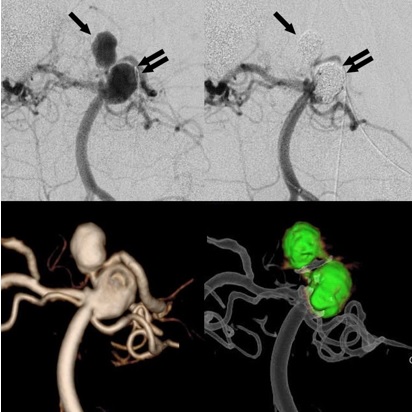

★脳動脈瘤に対するコイル塞栓術★

脳動脈瘤は脳の血管の一部がこぶ(瘤)状に拡張したものです。これが破裂すると「くも膜下出血」という脳の中の出血を引き起こし、非常に危険な状態に陥ります。脳動脈瘤は、たまたま脳の検査を行った際に発見されるもの(未破裂脳動脈瘤)もあれば、くも膜下出血を起こして発見されるもの(破裂脳動脈瘤)など様々です。

脳動脈瘤からの出血を予防するためには、従来は開頭して脳のしわを分け入り、瘤の首根っこをクリップで閉塞する「クリッピング術」が主流でした。しかし今から20年ほど前から、開頭せずに血管の中から脳動脈瘤の中にプラチナ製コイル(細い金属の糸くずのようなもの)を詰めこんで出血を予防する「脳動脈瘤コイル塞栓術」が世界的に普及し始めました。当院では当初より積極的に脳動脈瘤コイル塞栓術を行っており、現在では脳動脈瘤治療の第一選択となっています。

脳動脈瘤の形状は、まん丸なもの、いびつなもの、くびれ(ネック)がしっかりあるもの、寸胴のもの、全くネックのないものなど様々です。脳動脈瘤の中だけにコイルを収めるのが基本ですが、それが難しい場合は、風船を使ってコイルが出てこないように押さえ込んだり、2本のカテーテルからコイルを絡めるように収めたり、コイル突出防止用のステント(金属のメッシュ状の筒)を用いたりして、瘤の中にコイルを詰め込みます。コイルがうまく詰め込まれると、脳動脈瘤からの出血の可能性は著しく低下します。

当院では未破裂脳動脈瘤に対しても、破裂脳動脈瘤に対しても、コイル塞栓術を標準的治療法として行っています。未破裂脳動脈瘤の多くの例では、術後数時間から歩行可能で、数日で自宅退院が可能です。

(脳底動脈に多発する複雑な脳動脈瘤。周囲の枝を温存するように動脈瘤の中にコイルが留置された)